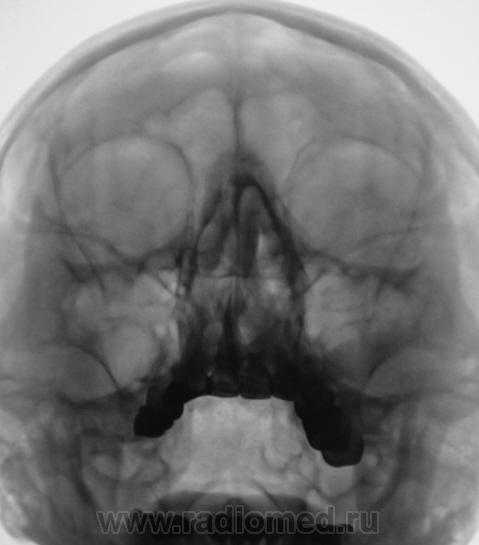

Пристеночное утолщение слизистой, выроженный отек носовых ходов - картина риносинуита.

А округлый контур затемнения в левой гайморовой пазухе не киста? Утолщение слизистой носа.

На кисту, судя по контуру и по объему затемнения не похоже, больше данных за отек, реком-ся контроль в динамике (через 3-4 недели) -отек "уйдет", а оценивать состояние слизистой носа - привилегия ЛОР-врачей

Состояние двузначное:с одной стороны есть как бы некоторое заокругление верхнего контура и локальность поражения; с другой - вытянутость формы затемнения, но, опять же таки - локальность. Т.е., с одной стороны локальность больше характерна для кисты, но не совсем, мягко говоря, характерна для гайморита. Как бы там ни было - клиент для КТ, цель - уточнение состояния слизистой.

На полипы совсем не похоже

По моему , киста